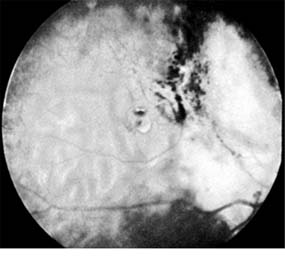

Retinoblastomas may exhibit outward (exophytic) or inward (endophytic) growth-either or both. The latter then extend into the vitreous (Figure 10-33). Both types gradually fill the eye and extend through the optic nerve to the brain and, less commonly, along the emissary vessels and nerves in the sclera to the orbital tissues. Occasionally, they grow diffusely in the retina, discharging malignant cells into the vitreous or anterior chamber, thereby producing a pseudoinflammatory process and mimicking retinitis, vitritis, uveitis, or endophthalmitis. Microscopically, most retinoblastomas are composed of small, closely packed, round or polygonal cells with large, darkly staining nuclei and scanty cytoplasm. They sometimes form characteristic Flexner-Wintersteiner rosettes, which are indicative of photoreceptor differentiation. Degenerative changes are frequent, accompanied by necrosis and calcification. A few will spontaneously resolve.

Figure 10-33

Figure 10-33: Endophytic retinoblastoma.